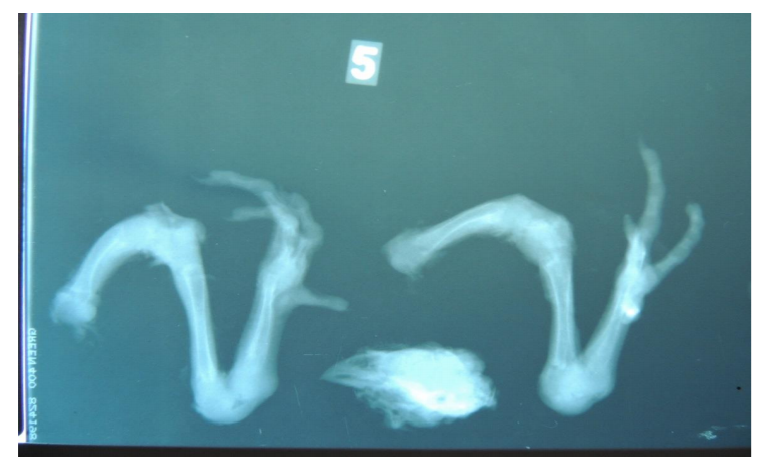

É possível separar as aves afetadas por problemas locomotores em diferentes categorias de acordo com a sua idade e/ou sistema produtivo. Frangos de corte são aves selecionadas para o rápido desenvolvimento, e comumente são afetadas por distúrbios do crescimento ósseo. São desordens que ocorrem durante o crescimento, sendo de natureza do próprio desenvolvimento da ave – ou metabólica, resultado em patologias de crescimento ou anormalidade da modelagem óssea (Fernandes, 2012). Os principais problemas nestas aves de rápido desenvolvimento são a deformidade angular e torcial, a discondroplasia, o raquitismo, a osteocondrose e a condrodistrofia.

Problemas locomotores em aves podem apresentar origem viral, como é o caso das artrites virais – sendo o mais comum o Reovírus aviário. Bactérias também são patógenos associados a problemas locomotores, sendo as principais associadas pertencentes aos gêneros Staphylococcus sp., Escherichia sp., Pseudomonas sp. e Salmonella sp. Devido à natureza dos sistemas de produção, artrites bacterianas apresentam um controle delicado, pois a completa desinfecção dos sistemas produtivos é um desafio.